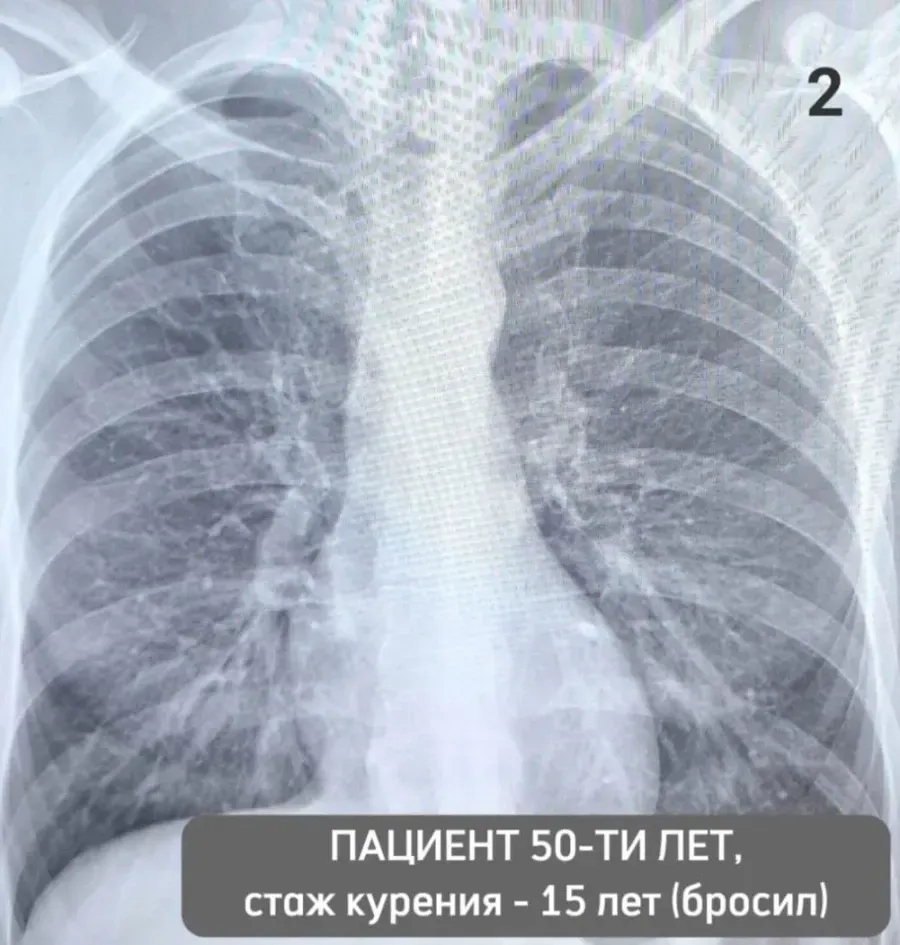

Изучение дозы излучения при рентгеновских исследованиях: визуализация